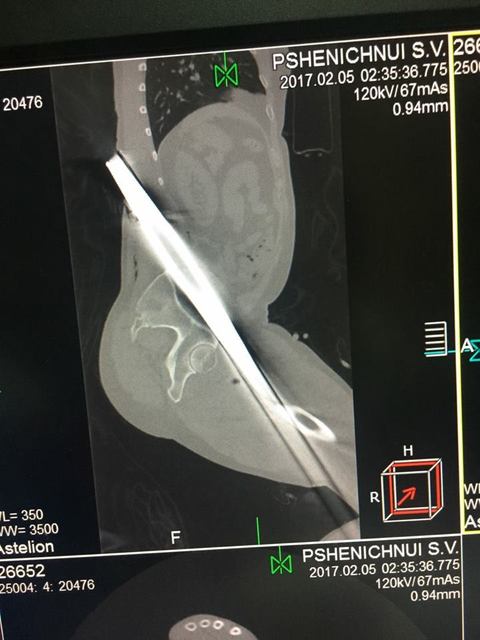

Заведующий приемно-диагностического отделения больницы имени Мечникова Петр Давыденко рассказал, что металлический профиль буквально насквозь проткнул мужчину.

«Итог: инородное тело левой голени, левого бедра, левой половины таза, левой половины поясничной области, открытый многооскольчатый перелом верхней трети левой большеберцовой кости, травматический шок», — отметил врач.

Первую медицинскую помощь пострадавшему оказали в Царичанке, после чего мужчину доставили в Мечникова. Осмотр немедленно провели дежурные травматологи, урологи, хирурги и нейрохирурги. Провели операцию по удалению инородного тела, ПХО ран, лапароцентез, а также объемное переливание препаратов крови.